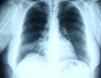

In June 2007 started complaining of cough with mucous sputum and wheezing. On physical examination, wheezing on pulmonary auscultation in the lower half of the right hemithorax was noted, with no signs of respiratory distress. Chest radiography showed a triangular-shaped opacity in the lower right lung region (Fig. 1). CT scan revealed atelectasis of the middle lobe and a nodular lesion in the middle lobar bronchus with 6mm diameter (Fig. 2). No abnormalities were detected through biochemical and haematological analysis. Lung function evaluation revealed mild obstructive syndrome. Fiber-optic bronchoscopy disclosed a polypoid, well-circumscribed, highly vascularized lesion, causing total obstruction of the medium lobe bronchus (Fig. 3). Its morphological appearance suggested a carcinoid tumor. Biopsy was not performed due to its associated bleeding risk and the patient underwent rigid bronchoscopy. Pathological examination of the tumor biopsy was inconclusive.